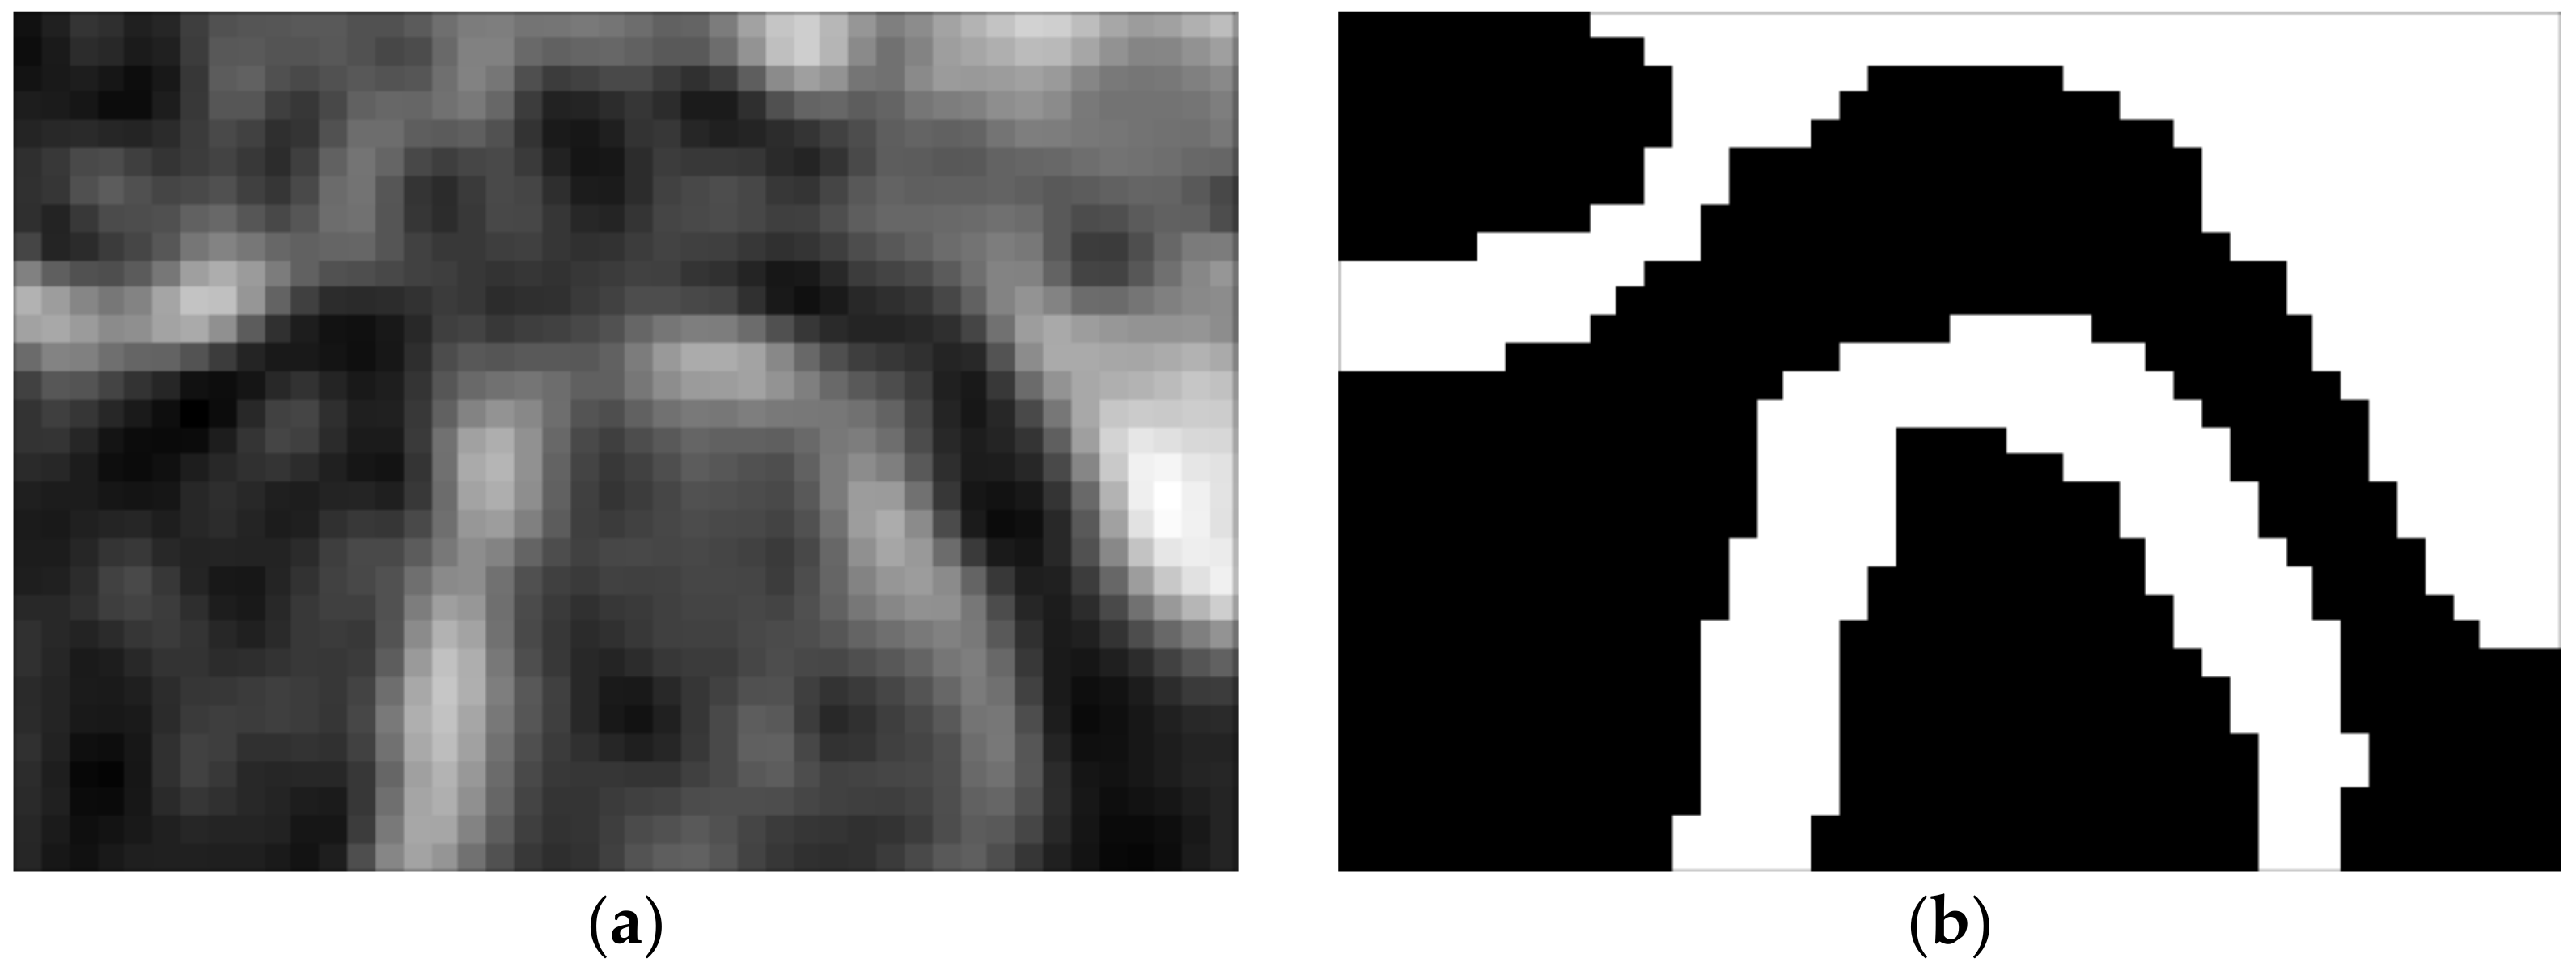

The identification of the TMJ head is based on a series of visualizations showing the patient’s skull in axial cross-section. The research was limited to the previously determined VOI region (becoming the Region of Interest—ROI on each slice). A series of views of consecutive cross-sections through the ROI containing the TMJ is presented in Figure 4. The initial assumption of the proposed algorithm is that the first (the uppermost) cross-section does not include any part of the TMJ acetabulum. In each slice, parts showing the bone have to be segmented. The segmentation is hampered by the fact that the CBCT image is usually noisy, the bones have a complex structure (they contain many voids) and the value of the voxels can significantly differ from the HU scale. Upon studying the set of images, the following observations were formulated:

Figure 4.

The example of axial slices (a) raw and (b) denoised and their histograms.

Let Si denote the ith slice in the VOI. The slices are numbered from the superior towards the inferior and are perpendicular to the z-axis. Considering the histogram hi of the voxel values within the Si, it can be noticed that there is no apparent voxel value at which the image can be thresholded to achieve the requested segmentation. It can also be seen that the image after smoothing has a more compact histogram—almost all values within the range are present. In the histogram, one can observe a single big peak, resembling the Gaussian curve. The peak starts from the lowest values and spreads until approximately −100. The part of the histogram to the right of this value is rather flat, with two or three faintly visible peaks. The pattern can be observed in the vast majority of the analyzed slices. Only the slices showing the bone just above the acetabulum (S0, S1) have more uniform histograms, although the left-most peak is still clearly visible on them. The idea of segmentation is based on using the Gaussian Mixture Model [39,40]. The model approximates the given distribution with a set of Gauss distributions. The parameters of Gaussians are determined using the EM algorithm [41,42]. The best results using GMM (Gaussian Mixture Model) were obtained where each slice was used separately for model training. An example of the achieved segmentation can be seen in Figure 5.